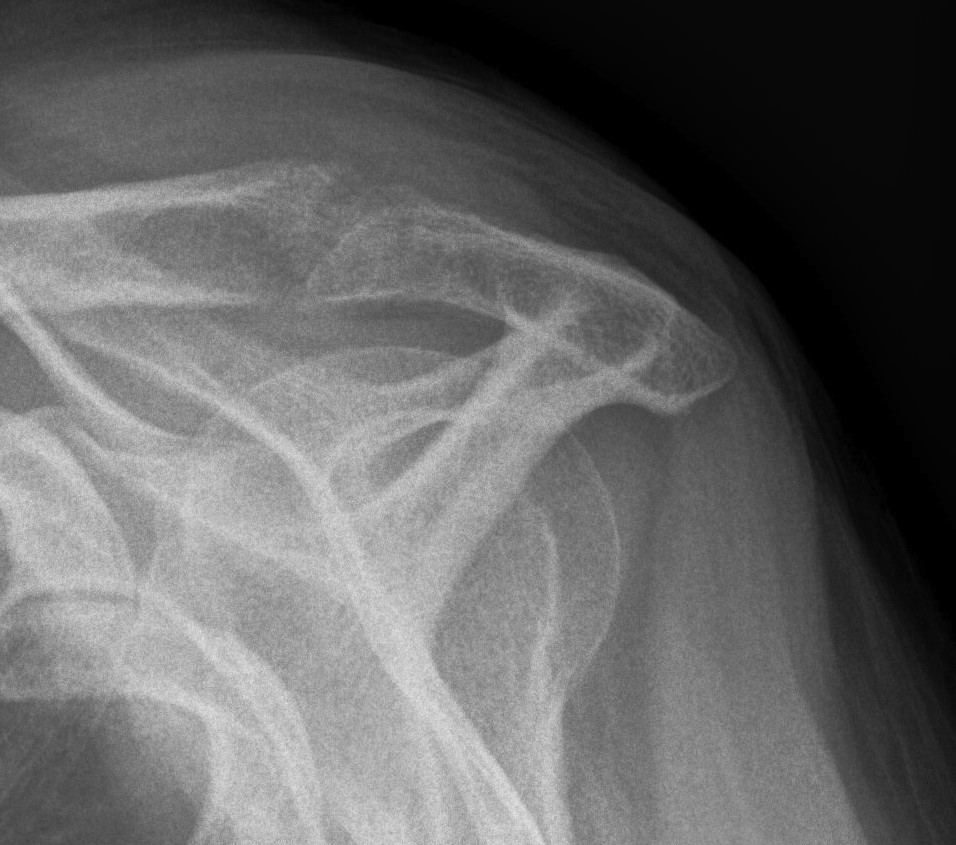

Type III acromial spur associated with a full thickness rotator cuff tear

X-ray

| AP | Supraspinatus outlet view | Axillary lateral |

|---|---|---|

|

Sclerosis greater tuberosity / acromion Lateral Acromion spur |

Acromial morphology | Os acromiale |

![]() |